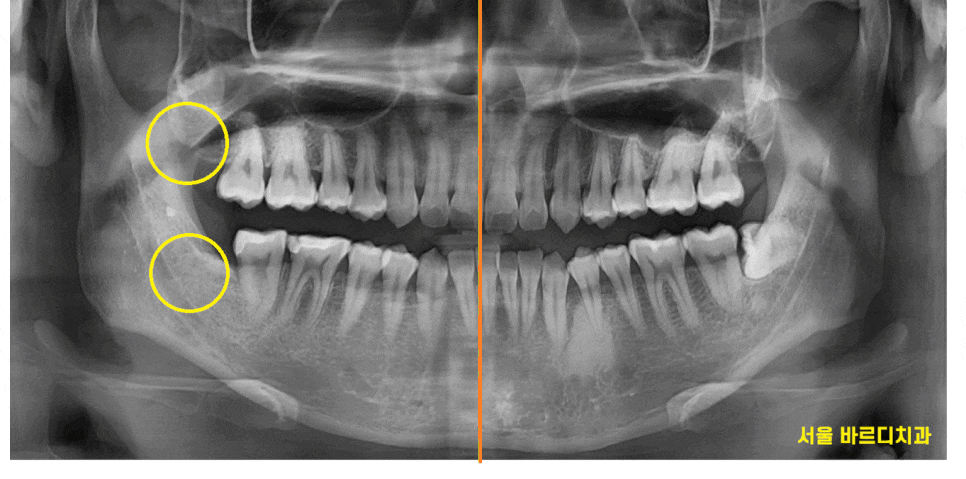

사진 속 4개의 사랑니가 있는데요.

한눈에 보기에도 아래쪽에 위치한 사랑니는

누워있죠~?

누워있고 숨어있는 사랑니는

발치 난이도가 증가하지만

예쁘게 잇몸 밖으로 올라온 사랑니,

윗니 사랑니는 수월하게 뽑을 수 있습니다 .